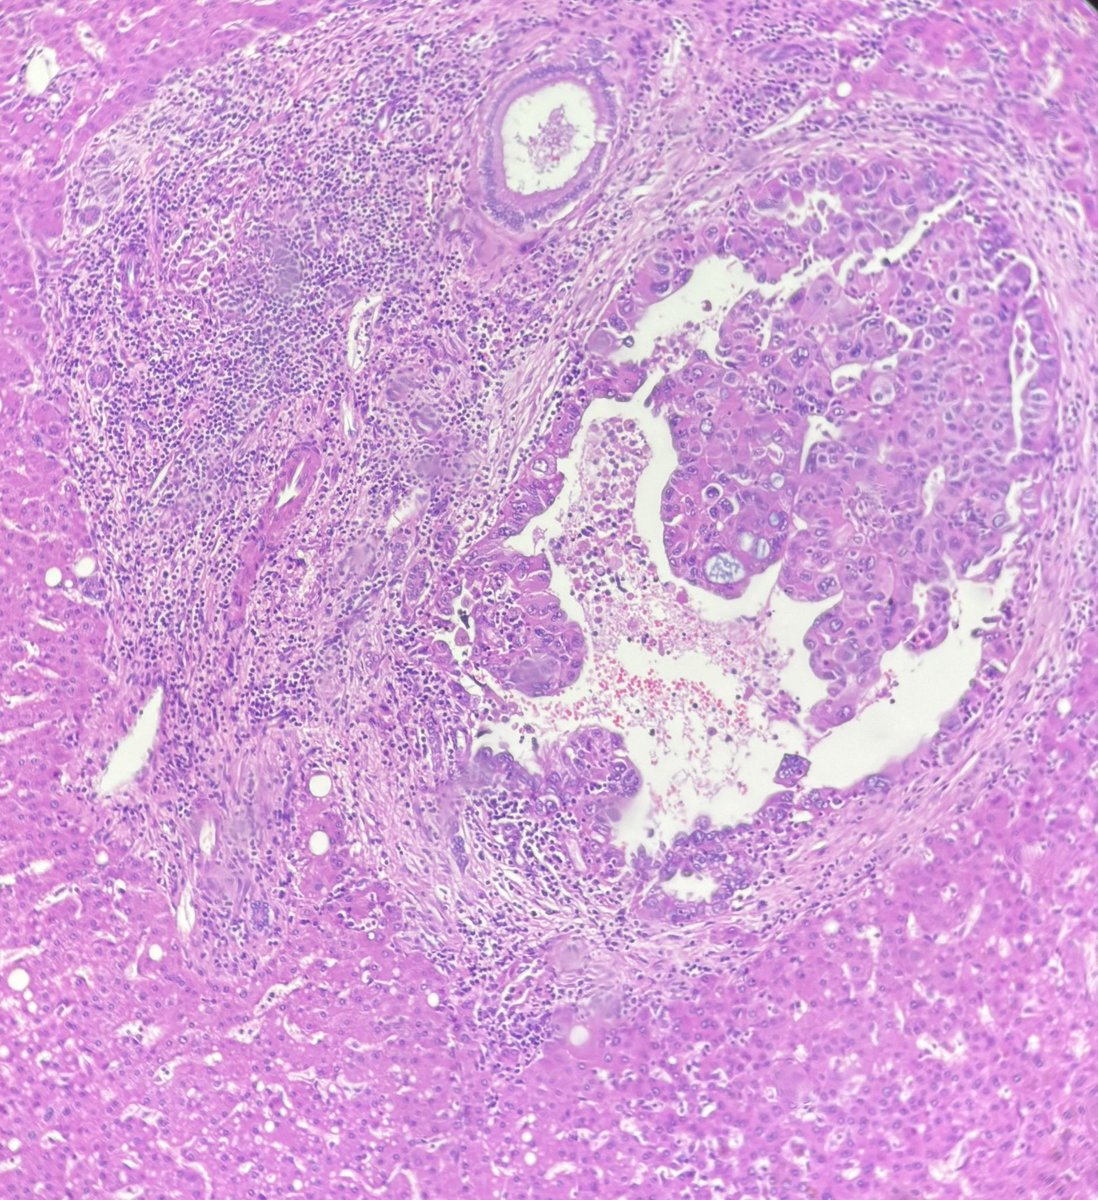

Hepatic surface deposit excision in post-neoadjuvant high-grade serous ovarian carcinoma. Liver capsular deposit (3 Γ— 1.5 cm) extends into the parenchyma and involves portal tracts. Should it be classified as parenchymal metastasis(pM1b) or considered as capsular deposit (pT3c)?